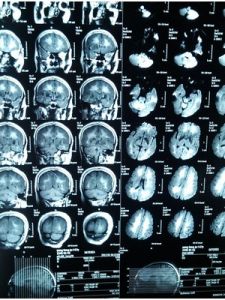

3.脊髓MRI示病變部位脊髓增粗,信號異常。

⑤電生理和MRI可發現腦內一些亞臨床病灶;MRI發現腦內白質異常信號。一些脊髓炎性脫髓鞘病變呈“假瘤樣”表現,其MRI表現出輕度占位效應,周圍有輕度水腫,可能有片狀出血信號,容易誤診為脊髓腫瘤。目前內科藥物治療效果不佳。